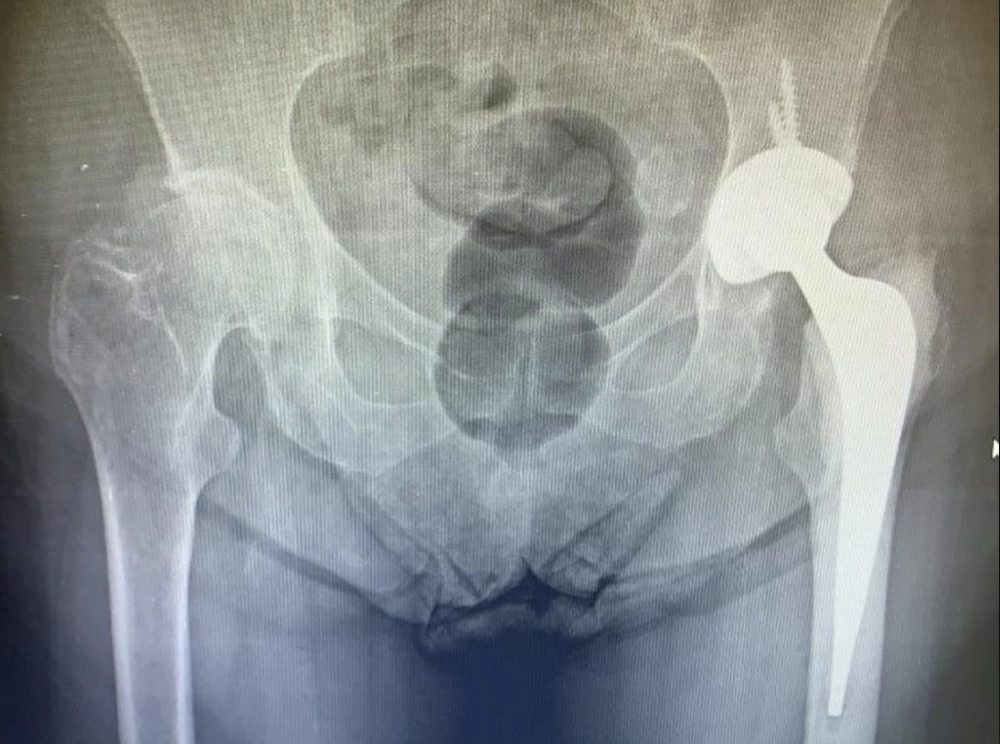

Rx demonstrando uma artrose grave de quadril esquerdo, paciente já com limitação e dor importante para caminhar e com dificuldade para atividades básicas do dia a dia.

Artrose severa do quadril esquerdo – seta.

Artrose severa quadril direito – seta.